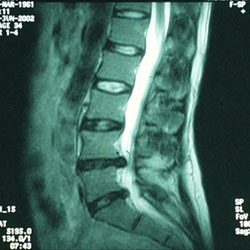

MRI of spine:

This degree of disc bulging of L4 and L5 (rare) will definitely cause symptoms but often the majority of the symptoms are from the secondary spread of muscle spasm and thus is more amenable to manual hands-on relief techniques.